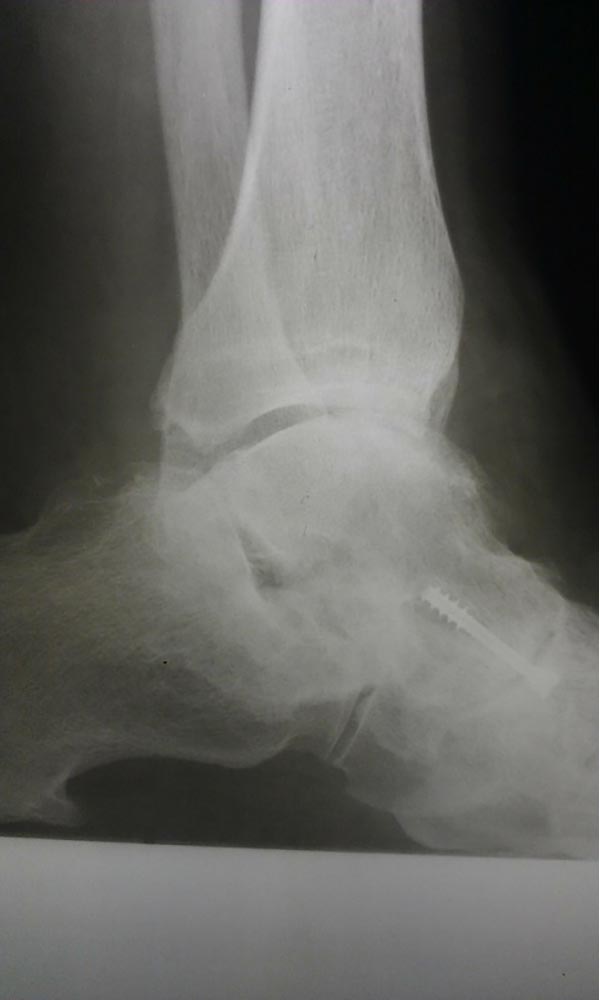

"Surgical misadventure" by another surgeon about 8 years ago. The wrong fixation was used for a flatfoot repair, & the deformity was not corrected. Patient came in with severe foot & ankle pain, with no arch at all. She was unable to play with her grandchild because the pain was so bad, & because she felt unsteady. The old hardware was removed, a lateral calcaneal lengthening osteotomy was performed along with a medial column/1st ray realignment. The ankle was painfully arthritic, & patient elected a total ankle replacement vs. an ankle fusion. She is now able to walk pain free & play with her grandchildren!

Ten years of severe ankle pain with a mal-positioned ankle fusion is now relieved! Patient is now walking with pain-free ankle motion!